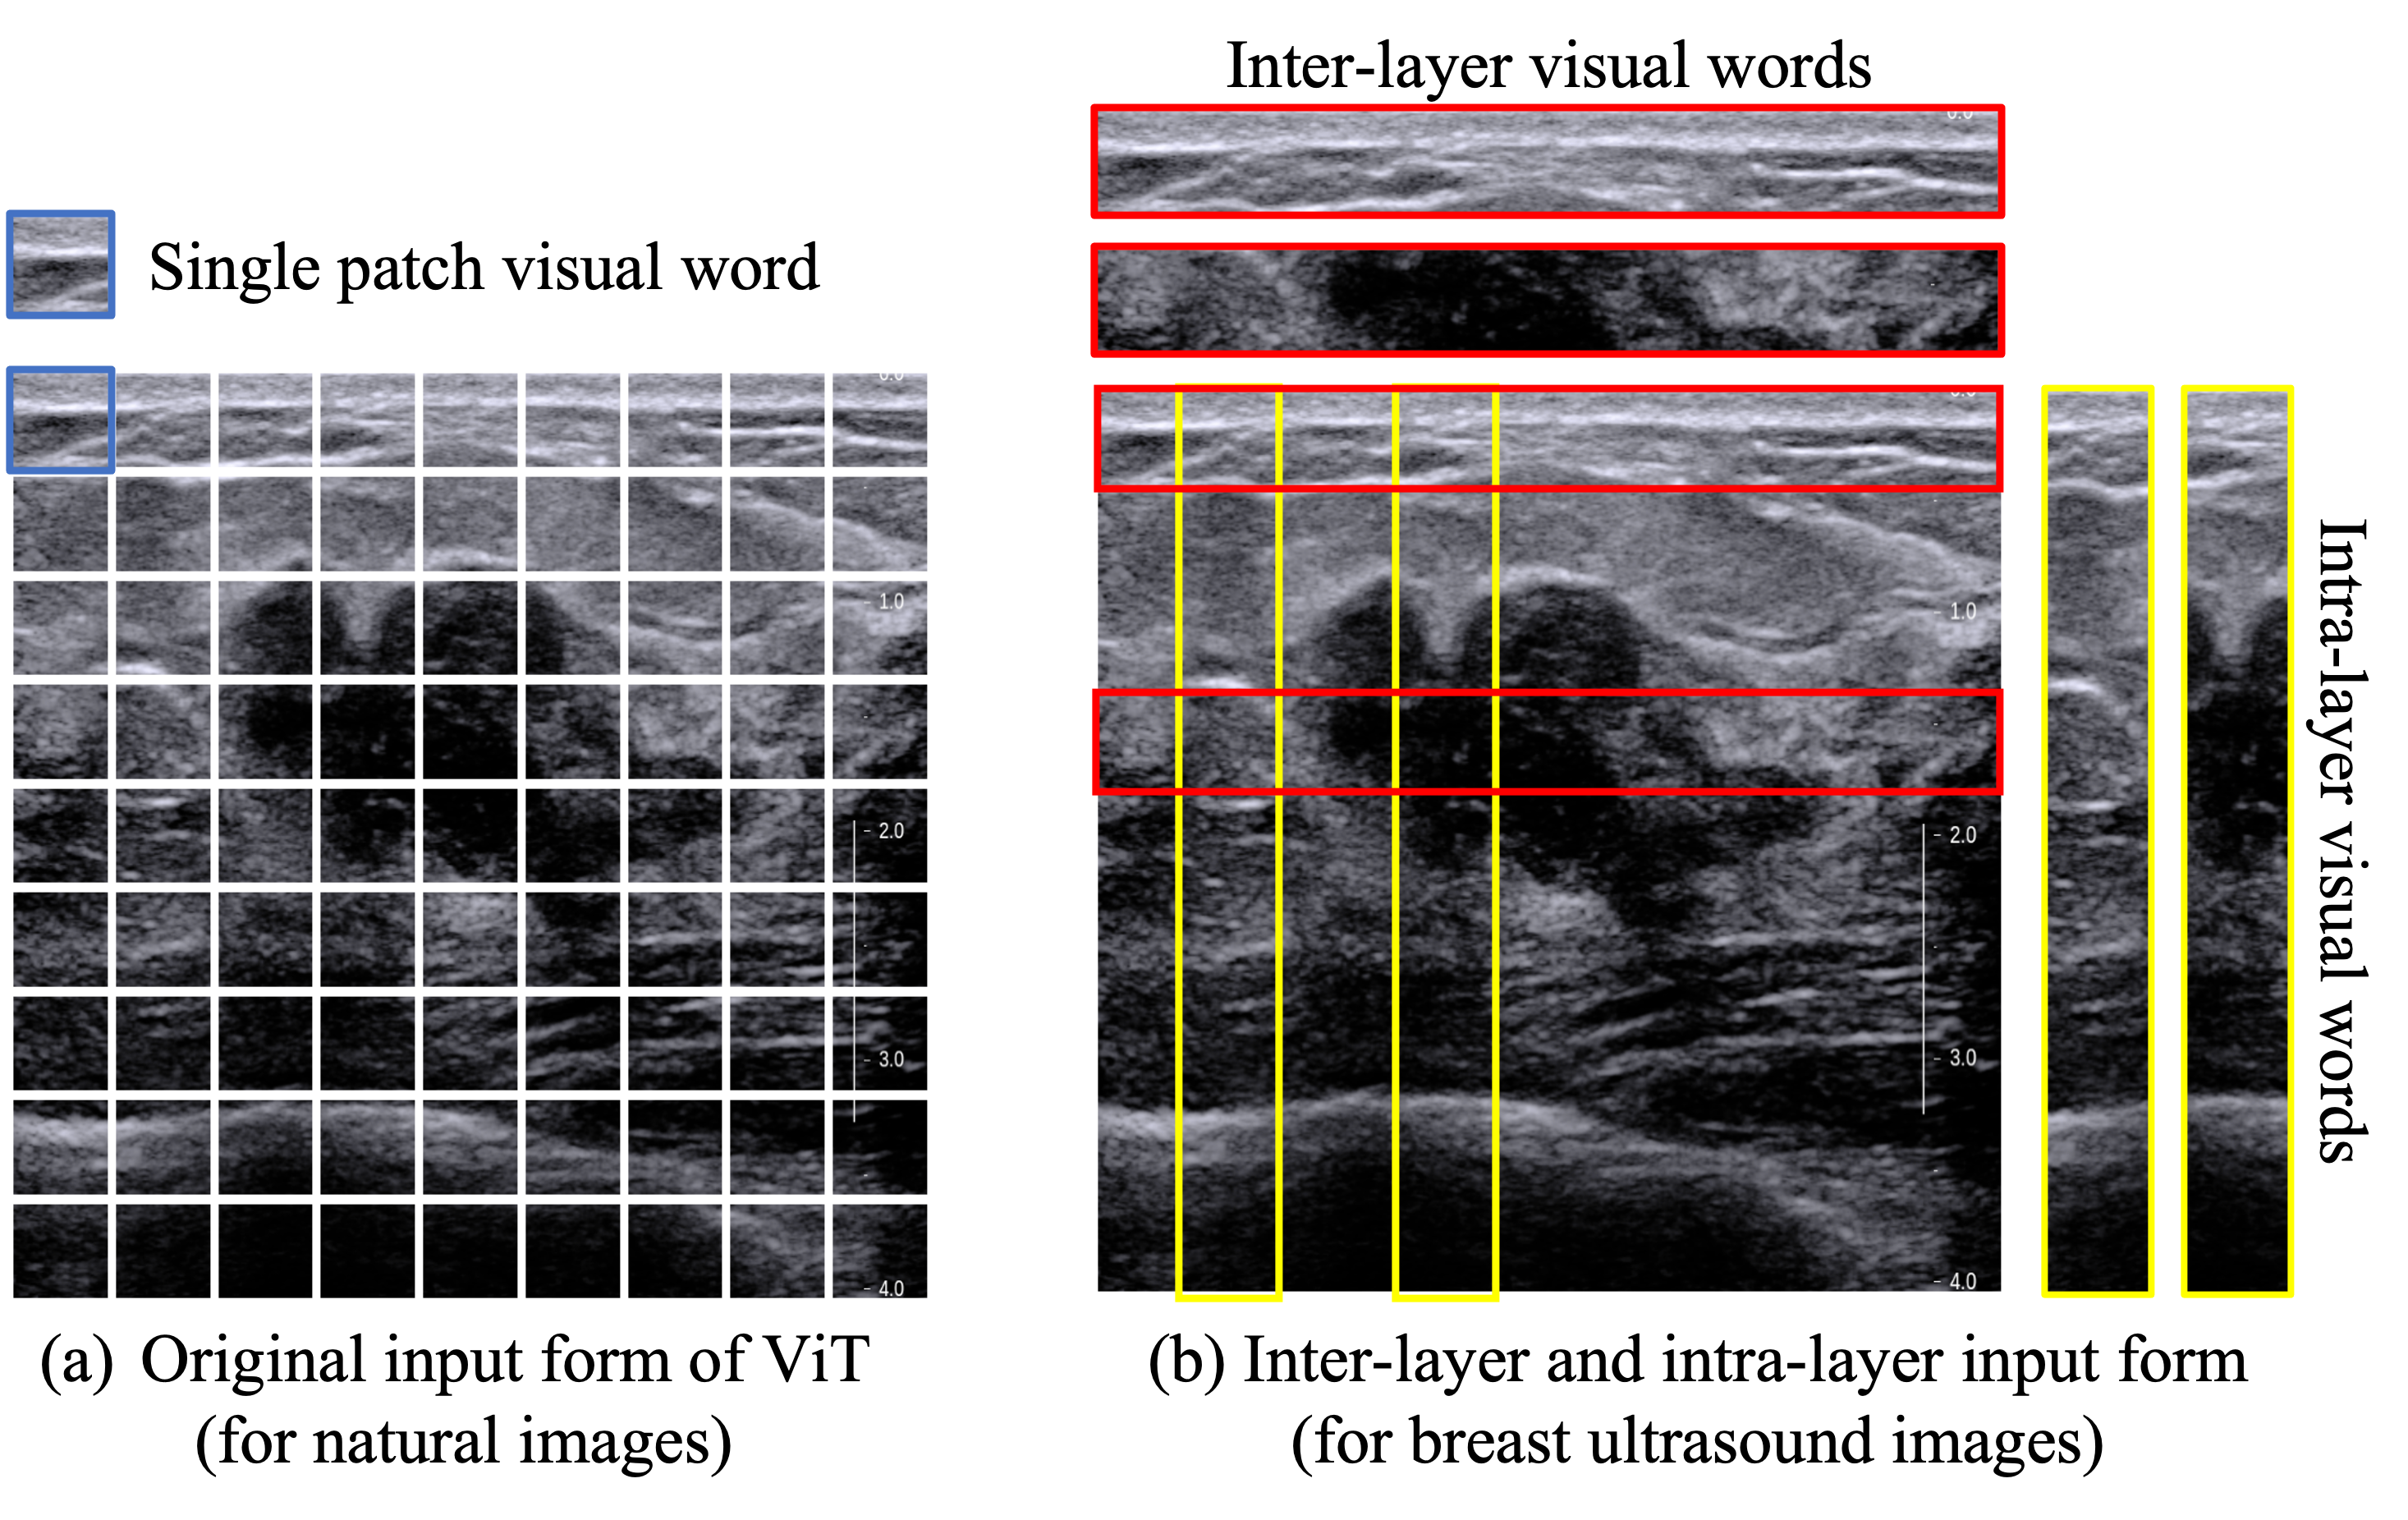

Refer to caption

Figure 3: Comparison of two embedding ways. (a) ViT tessellates the image into several 16×\times16 patches (visual words). (b) We formulate the anatomical structure of breast by the inter-layer visual words (horizontal strips) and the intra-layer visual words (vertical strips).

According to the ultrasound imaging principles and the anatomical structure of the breast, different breast tissues form different layers clearly in the ultrasound images, as shown in Fig. 1. The size, location and morphological appearance of the lesion and the spatial relationship with different layers determine the malignancy of the lesion. Conventional CNN models are good at extracting representative local features but show less effective spatial relationship representation ability. That is the reason why most of the existing breast cancer diagnosis algorithms in ultrasound images need a pre-defined ROI of the lesion to remove the redundant area and let the CNN model classify the ROI. The self-attention nature of the transformer introduces strong spatial relationships of each visual word, as shown in Fig. 3 (a). To further exploit the intra-layer and inter-layer spatial correlations in BUS, we formulate the problem by transforming the square-shape visual words into horizontal and vertical strips to bring the anatomical prior knowledge into the model, as shown in Fig. 3 (b).